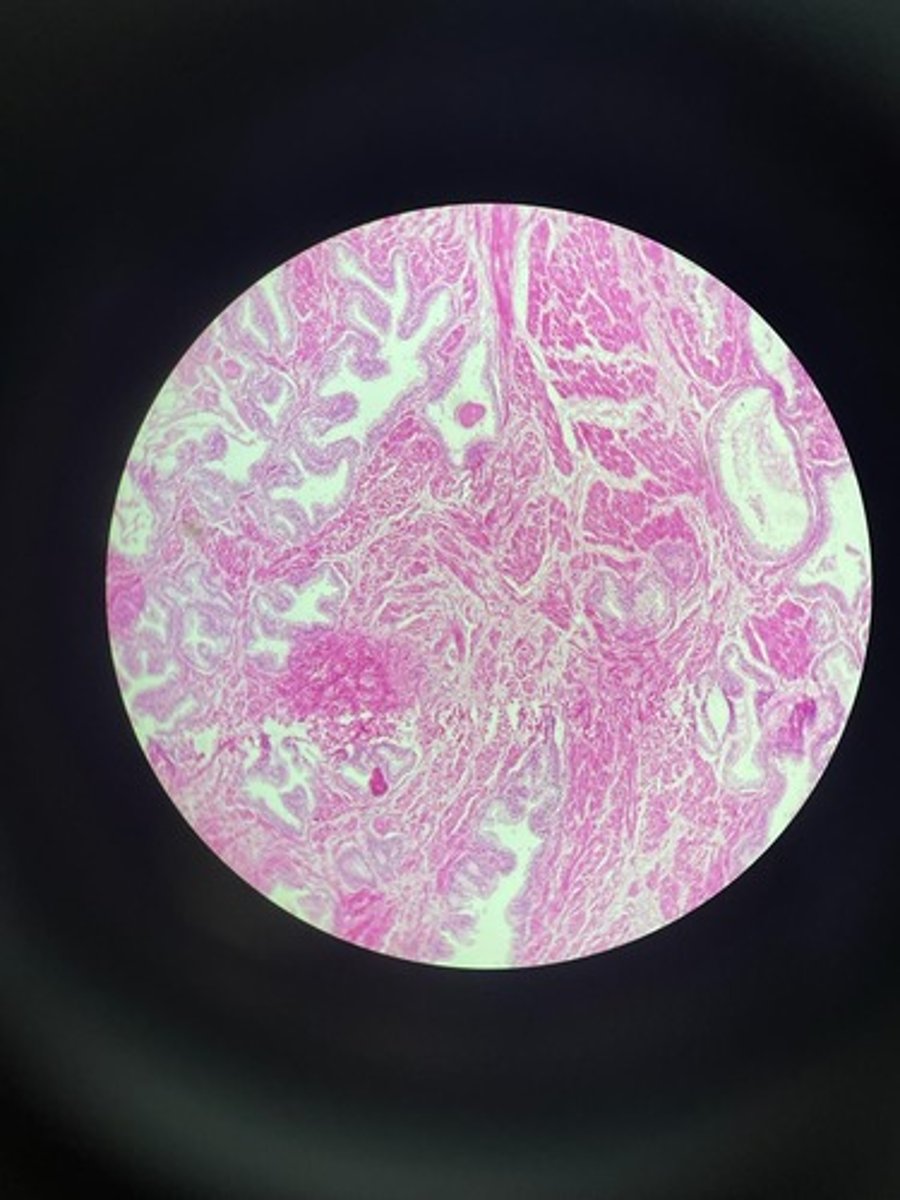

Uterus HE

Uterus HE

Uterus HE

Uterus HE